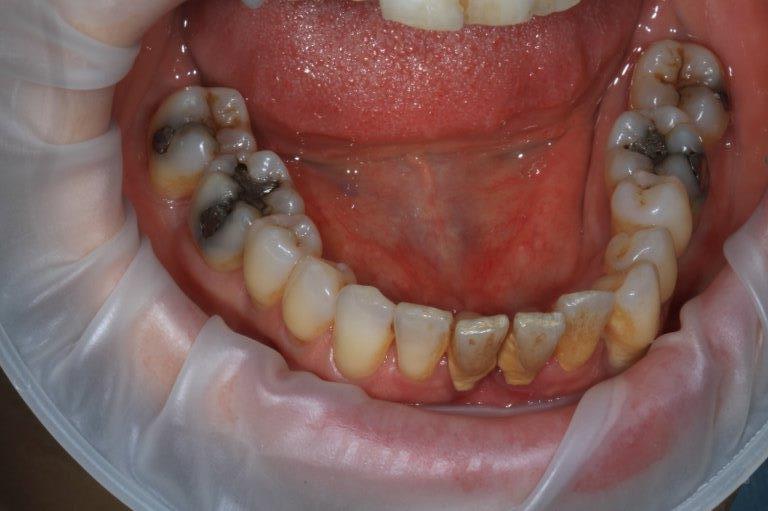

un peu de grain à moudre, toutes les critiques sont les bienvenues...

1ere séance,"nettoyage...", et après réflexion, plutôt que le nettoyage par le vide, attelle de contention pour le bloc antérieur mandibulaire, suppression de quelques contact très parasite sur les pm et canines, et réduction des incisives mandibulaire puis maxillaire... consignes de brossages / bain de bouche avec .... l'érythritol afin de ne pas mourir idiot... on verra ce que ça donne dans un cas relativement perdu d'avance.... merci Algi... enfin peut être : -))

C est dommage que l'on ne voit pas les dents en occlusion .

La 12 est en occlusion inverse et le secteur postérieur 20/30 aussi ?

" pcq ce truc ressemble comme 2 gouttes d eau à la résultante d' un sur contact antérieur de type cl2 associé à un décentrage latéral post unilatéral . à

gauche probablement ."

Une fois de plus ce n est pas un pb Paro mais bien occlusal .